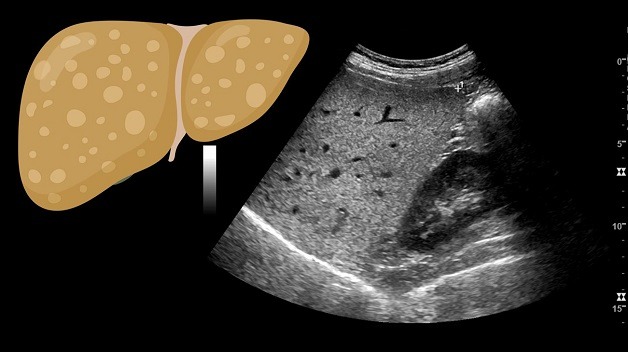

Trong quá trình siêu âm gan, bác sĩ sử dụng máy siêu âm và dụng cụ để thực hiện phát sóng siêu âm vào vùng bên phải của bụng để tạo ra hình ảnh gan. Những hình ảnh này được hiển thị trên màn hình, cho phép bác sĩ nhận biết các tổn thương ở gan. Siêu âm gan cho phép phân biệt giữa các cấu trúc khác nhau của gan, bao gồm thùy gan, phân thùy và hạ phân thùy. Tổn thương gan thường được nhận dạng dựa trên mối liên quan với các mạch máu như động mạch chủ, tĩnh mạch dưới, tĩnh mạch trên và tĩnh mạch cửa của gan. Trong trường hợp gan nhiễm mỡ, siêu âm thường cho thấy sự tăng độ sáng ở các vùng khác nhau của gan hoặc sự tăng độ sáng toàn bộ mô gan, gây mờ đi hình dáng của các cấu trúc mạch máu.

Hình ảnh siêu âm thường hiển thị sự xuất hiện của những vùng sáng tạo thành từng khu vực hoặc đốm sáng phân tán trên bề mặt gan. Các biểu hiện này thay đổi tùy theo mức độ nhiễm mỡ gan ở từng người. Khi gan bị nhiễm mỡ, siêu âm thường không thể nhận thấy hoặc không thấy được hệ thống mạch máu bên ngoài gan.

Ngoài ra, độ phản hồi âm của gan bình thường là bằng hoặc cao hơn so với vỏ thận và lách. Tuy nhiên, khi gan bị nhiễm mỡ, độ phản hồi âm của gan sẽ vượt trội so với vỏ thận và lách. Đồng thời, sóng siêu âm sẽ giảm sự rõ nét và không còn phân biệt được các cấu trúc trong gan.

Dựa vào những hình ảnh siêu âm này, bác sĩ có thể đánh giá mức độ nhiễm mỡ gan và từ đó xác định phương án điều trị phù hợp cho bệnh nhân.